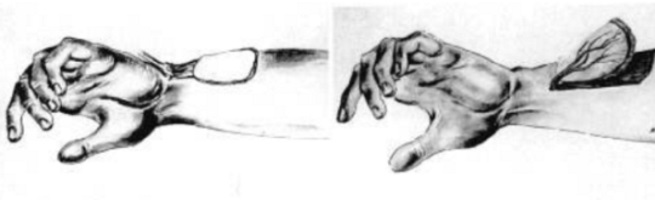

Ефективність передопераційної діагностики з використанням КТ-ангіографії при реконструктивних втручаннях на нижніх кінцівках

Авторы: С. В. Слєсаренко, П. О. Бадюл, С. О. Мунтян, К. С. Слєсаренко, О. О. Ковбаса Статья опубликована в журнале: Клін. хірургія. – 2016. – № …